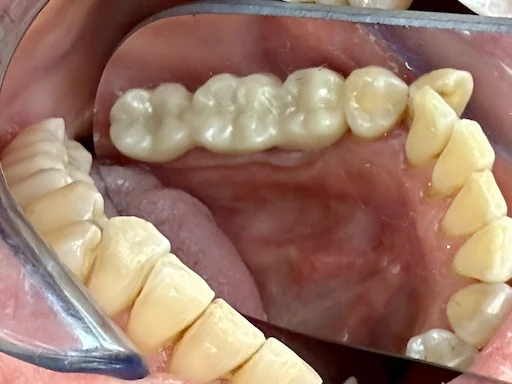

Patientenfall 45, 46, 47 - Prothetik

Schritt 3

Die prothetische Versorgung erfolgt mit verblockten Kronen, die auf den Implantaten verschraubt werden.

(Einer verschraubten Konstruktion sollte immer der Vorzug gegeben werden, da keine Entzündungsgefahr durch Zementreste wie bei einer geteilten und zementierten Konstruktion besteht.)